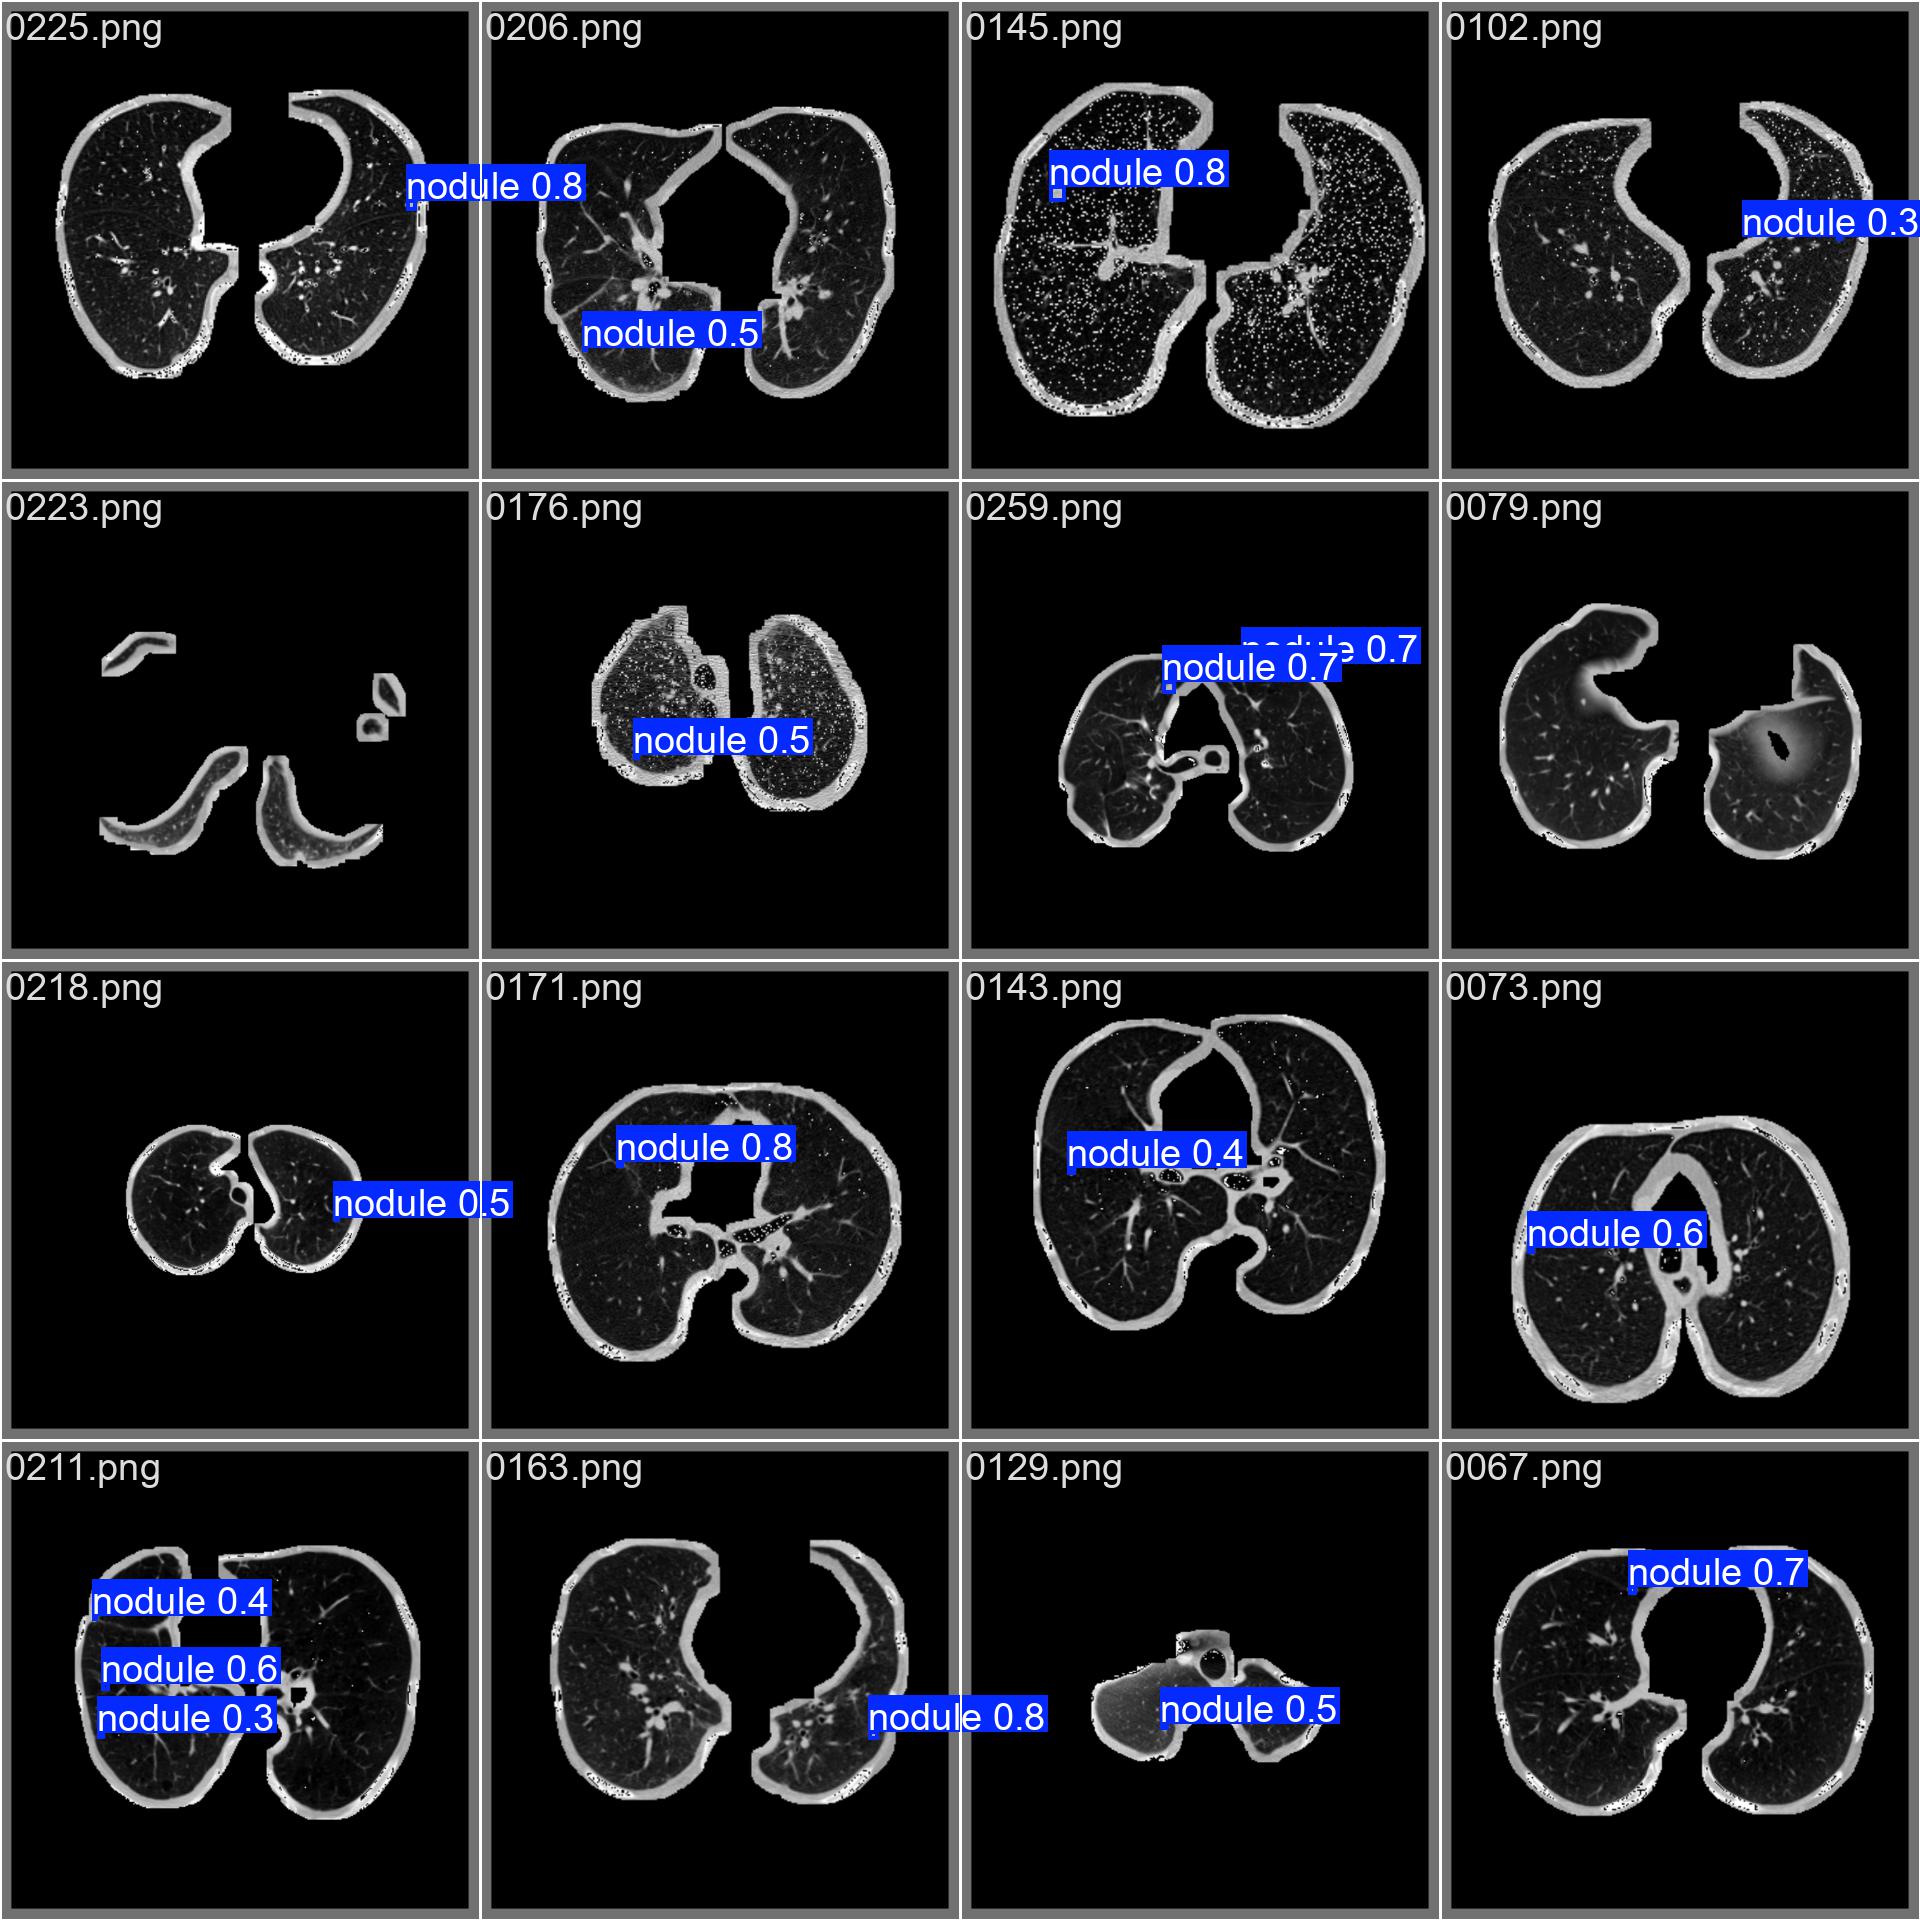

当iou阈值为0.5的时候,模型在测试集上的map可以达到68.1%。下面是一个预测图像,可以看出,我们的模型可以有效的预测出这些尺度比较小的交通目标。